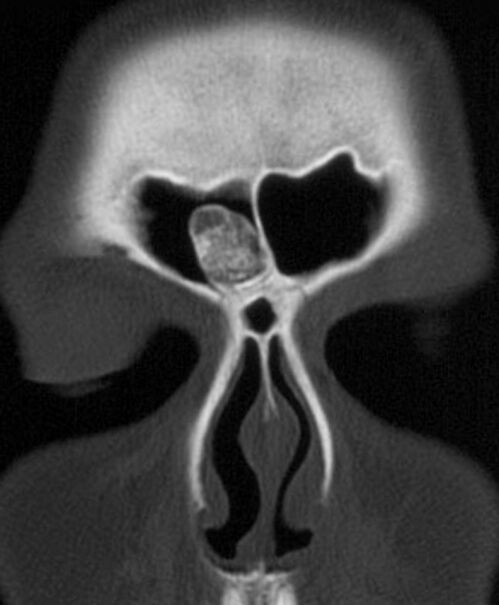

Диагностика

Диагноз остеомы ставят на основании клинико-рентгенологических данных. Дифференциальный диагноз между хроническим остеомиелитом и остеогенной саркомой легко установить на основании рентгенологической картины и течения заболевания.